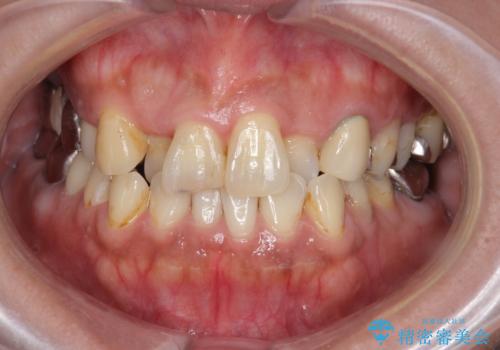

前歯が気になる。ブリッジによる治療。

- 前歯のがたつきが気になるとの事で来院。

①矯正を行う(費用と時間がかかる)

②左右2番の歯を抜歯してブリッジの被せ物を入れる(矯正ほど費用、時間はかからない)

という計画を立てて患者様に選んでもらいました。

②の方を選択されましたので被せ物治療を行いました。

また、左上の犬歯の根の再治療も行いました。